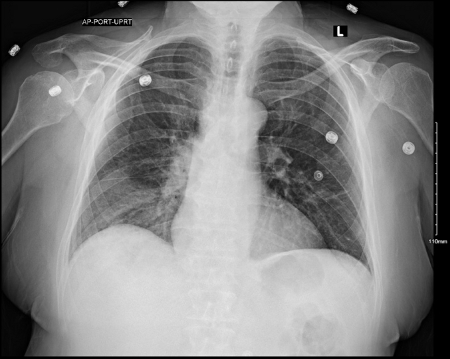

chest x-ray

Test

To evaluate for lobar infiltrate. If infiltrate is absent, but clinical suspicion remains, laboratory tests should be ordered. [Figure caption and citation for the preceding image starts]: Chest x-ray showing Legionella infection: right lower lobe infiltrate consistent with pneumonia (arrow). Legionella confirmed positive with urinary antigen testFrom the personal collection of Dr Forest W. Arnold; used with permission [Citation ends].

[Figure caption and citation for the preceding image starts]: A portable anterior/posterior chest radiograph showing a right lower lobe infiltrate consistent with Legionnaire's diseaseFrom the personal collection of Dr Forest W. Arnold; used with permission [Citation ends].

Result

Legionnaires' disease: lobar infiltrate; Pontiac fever: normal